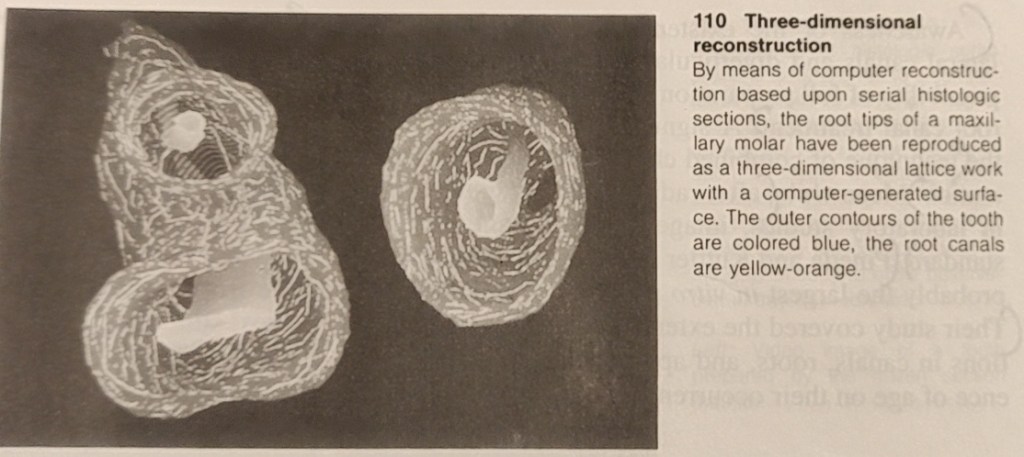

The first detailed systematic description of root canal anatomy found in the literature is by Carabelli (1844). The same manner of representation with longitudinal and transverse sections in different planes is still used in modern textbooks (eg., Cohen and Burns 1994). Some of these illustrations go back to the original sections and serial sections (Black 1902; Miller 1904). In addition to direct observation with the unaided eye and the microscope, the chemical dissolution method has provided much valuable information. In this process the tooth is opened, the pulp digested, and the empty pulp space filled. The famous Swiss pulp researcher Hess (1917) perfected this technique in which he filled the pulp space with vulcanized India rubber and then dissolved the surrounding tooth substance with 50% hydrochloric acid. This acid dissolution preparation showed the complex branching of the pulp tissues and, with it, the root canal system. Whereas the previous sections, slides, and drawings were only two-dimensional, now for the first time it was possible to see a spatial representation of the entire root canal system. Hess studied 2800 teeth of the permanent human dentition and his student Zurcher (1922) studied deciduous teeth. Together they gathered statistical data on the number of canals and their ramifications.

While histologic sections have long provided information on the structure of the root canal and the pulp tissue, Meyer (1955-1970) set new standards. From special sections of all 16 types of permannet teeth he made 50x scale models of the apical canals (the last 6 mm of each) of 800 teeth by projecting the circumference of the canals and building wax models layer by layer. This study further clarified the complexity of the pulp space, from then on called the root canal system (Meyer 1955 b, 1960).